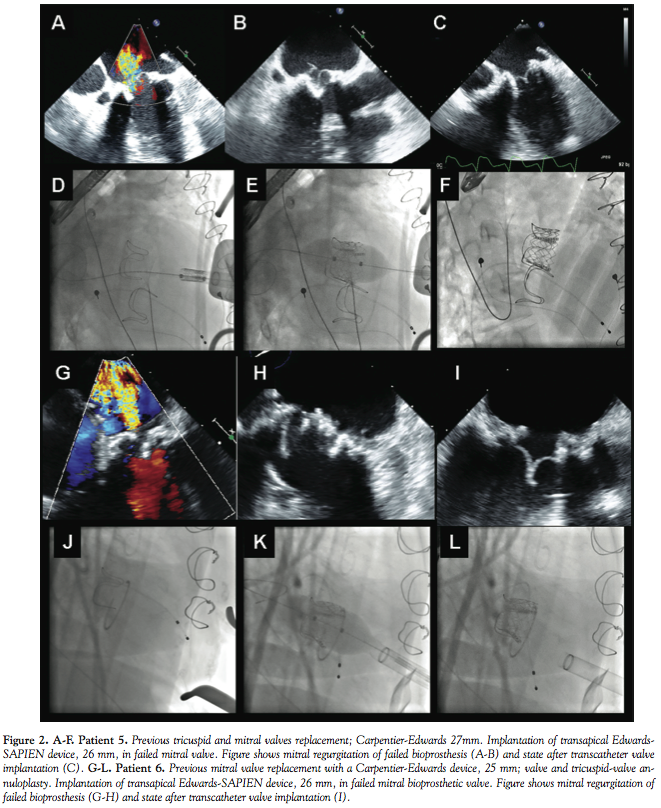

Four procedures were performed with a CoreValve device (2 transfemoral access, 2 transaxillary access) and 2 with an Edwards-SAPIEN device (transapical access). All VIV procedures were technically successful (Figures 1 and 2). None of the patients had vascular problems, stroke, or other major complications. In the aortic procedures, the mean valve gradient decreased from 43 ± 9.3 to 12.3 ± 8.6 mmHg (p < 0.001). Patients were discharged 5.2 ± 1.3 days after the procedure. Thirty-day survival was 100%. There was a significant improvement in patient functional class from before the procedure (0% class I/II, 50% class III, 50% class IV) to after the procedure (66% class I, 33% class II, 0% class III/IV) (p < 0.001).